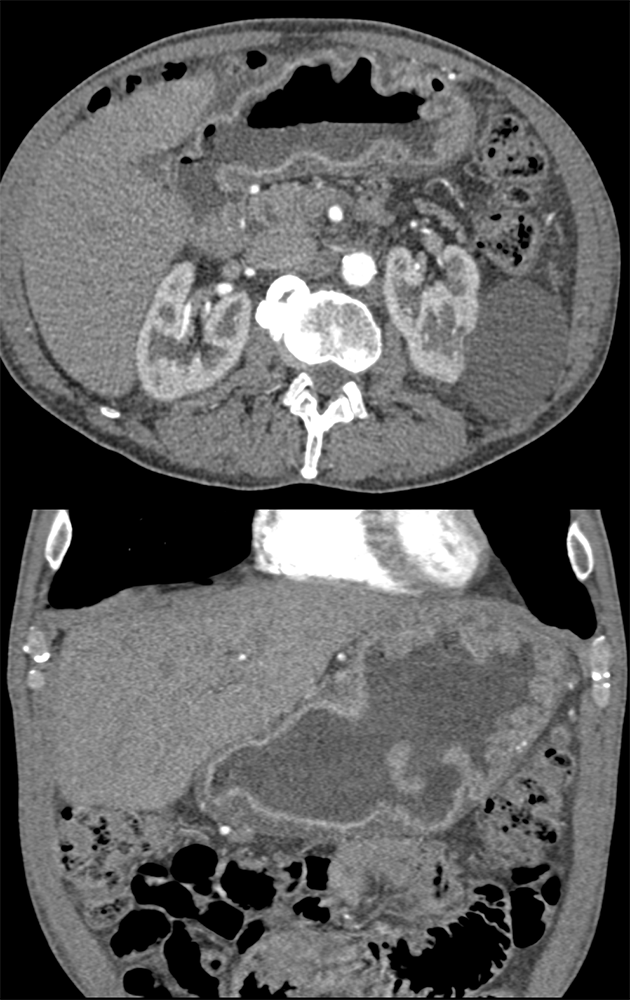

“In our patient, the findings of prominent mucosal folds extending from the pylonic channel on upper gastrointestinal series and the thickened antral wall on CT scans correlate well with the known pathologic appearance of gastnic antral vascular ectasia. Histologically, antral thickening results from a combination of foveolar and fibromuscular hyperplasia. Grossly, the antral fold prominence appears to result from bunching of the mucosa in the thickened, hypercontractile antrum.” Gastric antral vascular ectasia ("watermelon stomach"): radiologic findings. Urban BA, Jones B, Fishman EK, Kern SE, Ravich WJ. Radiology. 1991 Feb;178(2):517-8. |

“Gastric antral vascular ectasia primanily affects women (9:1 female-to-male ratio) aged 56-76 years, and is associated with liver cirrhosis (37%) and achlorhydnia (35%). The usual symptoms are iron-deficiency anemia and melena due to chronic gastrointestinal bleeding from the dilated, superficial, and easily traumatized vessels. Antrectomy is curative, but endoscopic treatment with heat probes or lasers has shown promise.” Gastric antral vascular ectasia ("watermelon stomach"): radiologic findings. Urban BA, Jones B, Fishman EK, Kern SE, Ravich WJ. Radiology. 1991 Feb;178(2):517-8. |